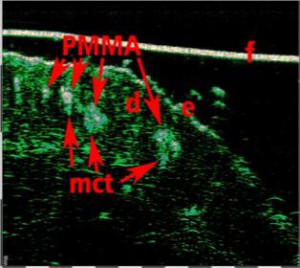

-Έγχυση Πληρωτικών Υλικών (Fillers)